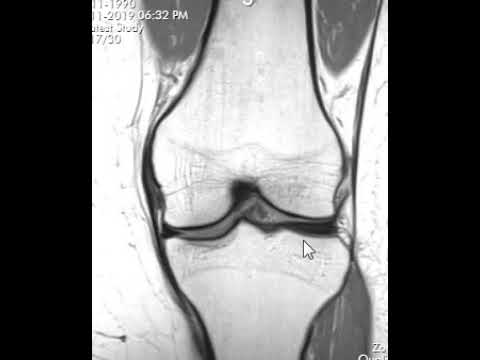

Как расшифровать МРТ колена | Первый взгляд на МРТ